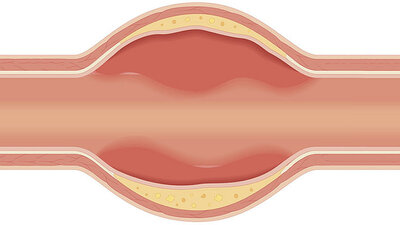

Herr Professor Czerny, die Aorta ist die große Arterie, die oben vom Herzen abgeht und dann in einem Bogen in den Bauch führt. Von ihr führen zahlreiche Gefäße ab, die den Körper mit sauerstoffreichem Blut versorgen, deshalb wird sie auch Hauptschlagader genannt. Sie ist also ein wichtiges Gefäß. Jetzt wurde sie sogar als eigenständiges Organ eingestuft. Warum?

(lacht) Eine ganze Menge! Zunächst einmal entsteht die Aorta im Embryo aus unterschiedlichen Ursprüngen. Das heißt, sie hat in manchen Abschnitten tatsächlich eine andere Zusammensetzung als andere Gefäße. Dann hat sie im Aortenbogen noch sogenannte Barorezeptoren, das sind Druckrezeptoren. In der Aorta misst der Körper also gewissermaßen selbst den Blutdruck – und nimmt dann entsprechende Anpassungen vor, er stellt etwa die Gefäße weiter oder enger. Die Aorta ist ganz klar ein eigenes Organ – und sollte als solches auch behandelt werden.

Die Aortendissektion ist eine der häufigsten Schäden, die in der Aorta auftreten. Sie ist potentiell lebensbedrohlich: Es handelt sich um einen Riss der inneren Schicht, der dazu führt, dass Blut in die Gefäßwand eindringt, diese dadurch aufdehnt und einreißen kann.